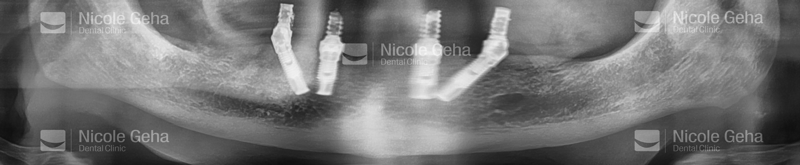

After implant placement